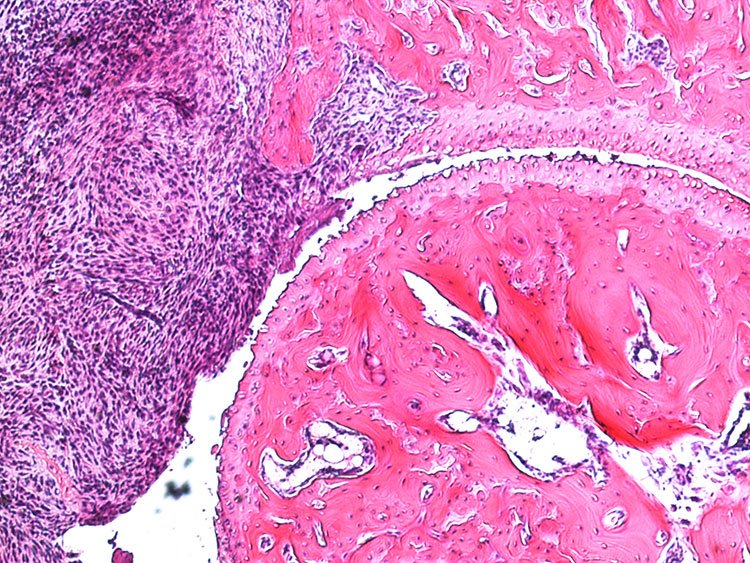

In the collagen antibody-induced arthritis (CAIA) model mice injected with collagen type II antibodies exhibit joint inflammation and other pathologies similar to those experienced by patients with rheumatoid arthritis. This model was based on the presence of anti-collagen type II antibodies in patients with RA and has become commonly used in studies aimed at examining the pathology of rheumatoid arthritis. Prior to our work, however, this model had not been used for assessment of arthritis-induced pain (nociception). We found that in this model mice developed mechanical hypersensitivity prior to any signs of joint inflammation, which persisted for several weeks after the resolution of joint inflammation. This mimics the onset of pain in RA patients as well as its persistence in individuals whose other symptoms are well controlled. Using behavioral, electrophysiological, molecular and imaging techniques along with transgenic animals, we are currently focusing on studying the mechanisms underlying pain prior to RA onset and pain that persists during phases with low disease activity.

Immune complex (IC) is composed of aggregates of antibodies bound to their soluble antigens. ICs regulate inflammatory processes by activation of Fc receptors (FcR) expressed on various inflammatory cells and the complement system. Importantly, we and others have shown that sensory neurons express FcγRI and FcγRIIb and that IgG in IC formation can directly activate nociceptors, independent of inflammatory cells and the complement system. Our studies show that the FcγRI is responsible for the early pain-like behavior we see in the CAIA model. We are currently investigating the role of FcγRs expressed on DRG cells as an additional novel pain mechanism in RA (and other autoimmune diseases) in which autoantibodies may act as pain-inducing molecules independent of the inflammatory process during active disease. This project has also a strong translational potential as we discovered the presence of FcγRIII on human adult DRGs. This could lead to novel therapeutic strategies for pain not only for RA, but also for other autoimmune diseases where there are accumulation of IgG and formation of immune complexes in innervated tissues, such as the DRG.